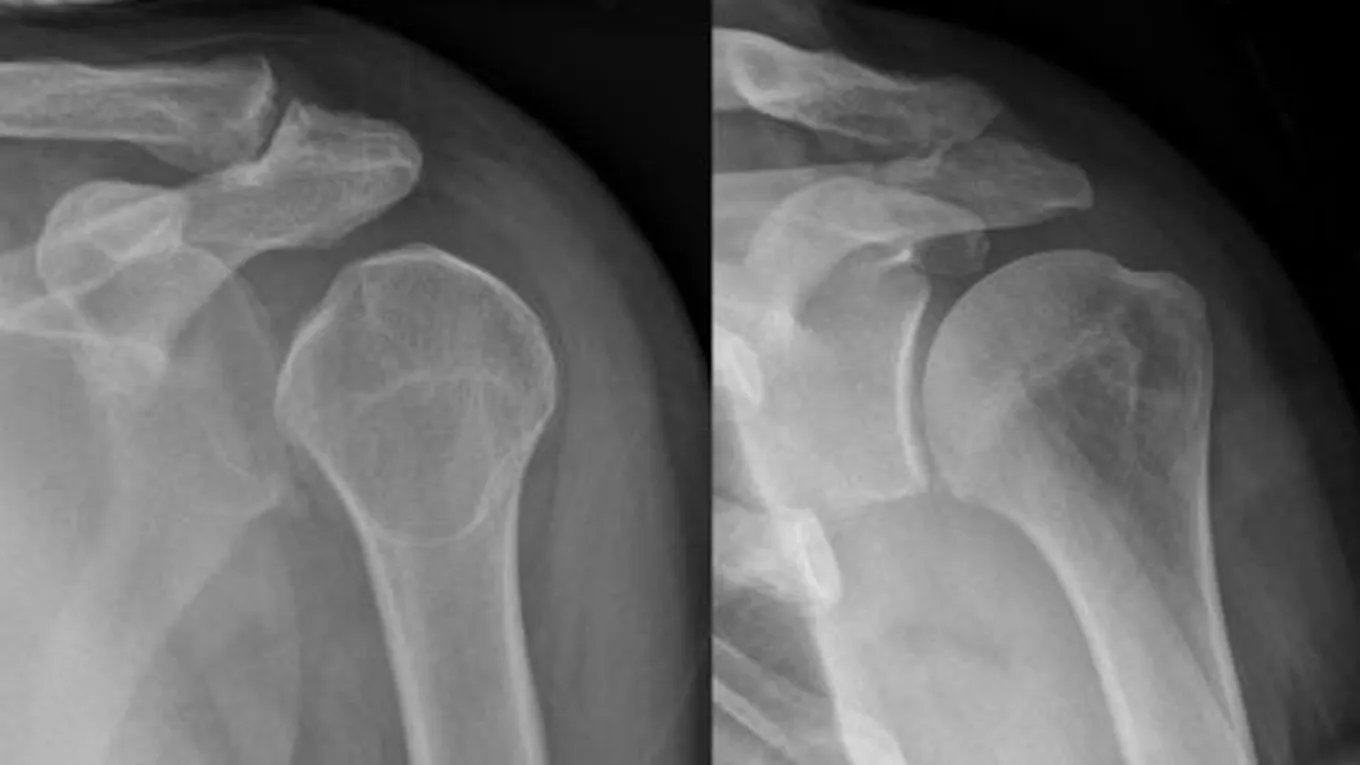

أعراض الإصابة بخلع الكتفيحدث خلع الكتف نتيجة خروج مفصل اليد العُلوي عن تجويف الكتف؛ نتيجة السقوط عليه، أو تعرُّضه للإصابة، ويُرافق خلع الكتف ظهور العديد من

يحدث خلع الكتف نتيجة خروج مفصل اليد العُلوي عن تجويف الكتف؛ نتيجة السقوط عليه، أو تعرُّضه للإصابة، ويُرافق خلع الكتف ظهور العديد من الأعراض، وفيما يأتي بعض منها:[1]

- تشوُّه الكتف؛ أي ظهور بروز في الجزء الأماميّ، أو الخلفيّ من الكتف.